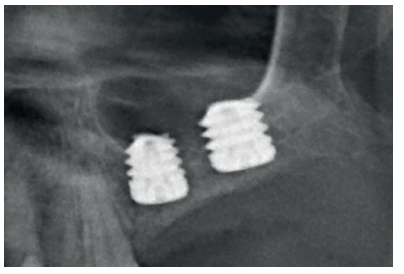

After two months, the dental cone-beam showed the perforation had closed completely but the residual bone volume provided 2 mm of bone height only, which was insufficient to insert the implants (Figures 3 and 4).